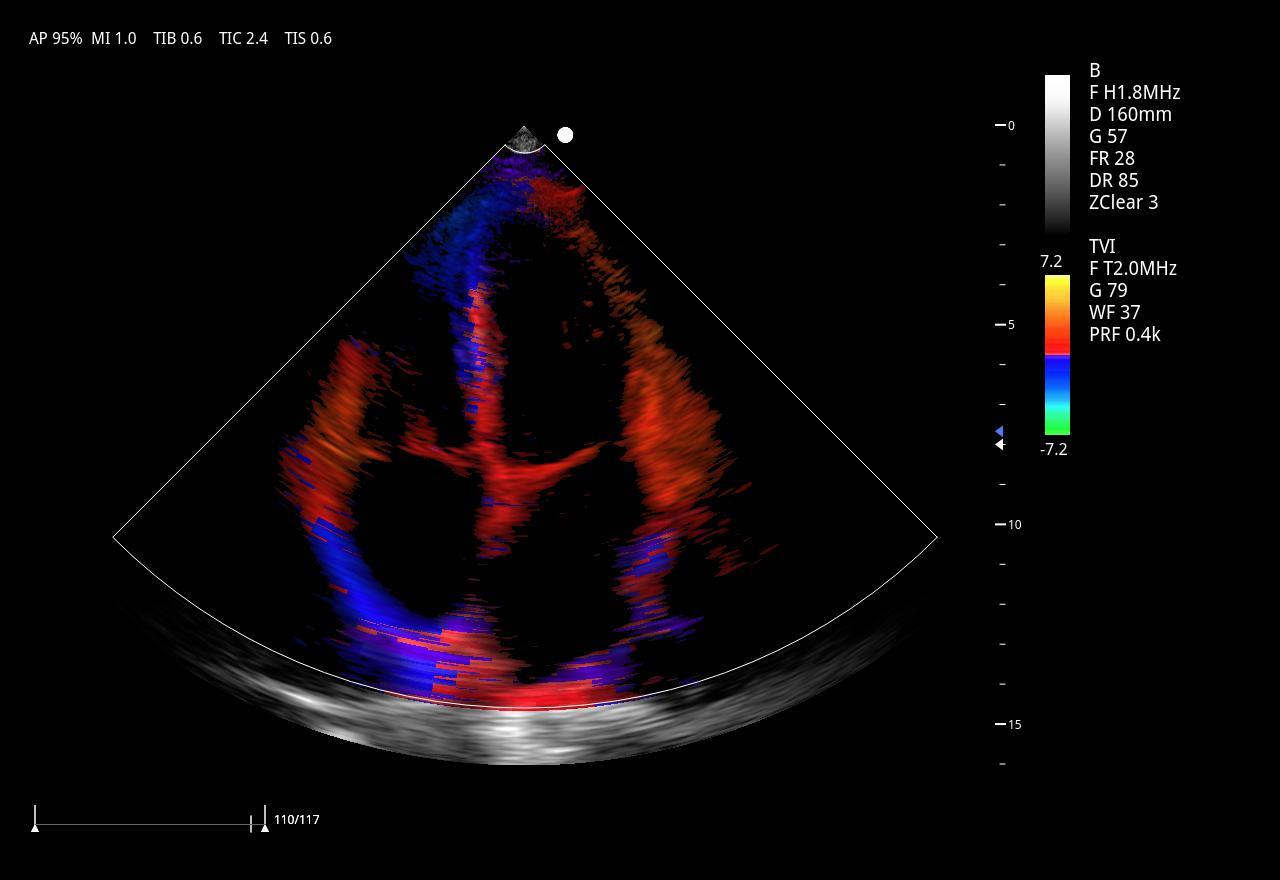

Imágenes clínicas extraordinarias

| Aplicaciones | Cardiología, abdomen, vasos sanguíneos, estudios generales |